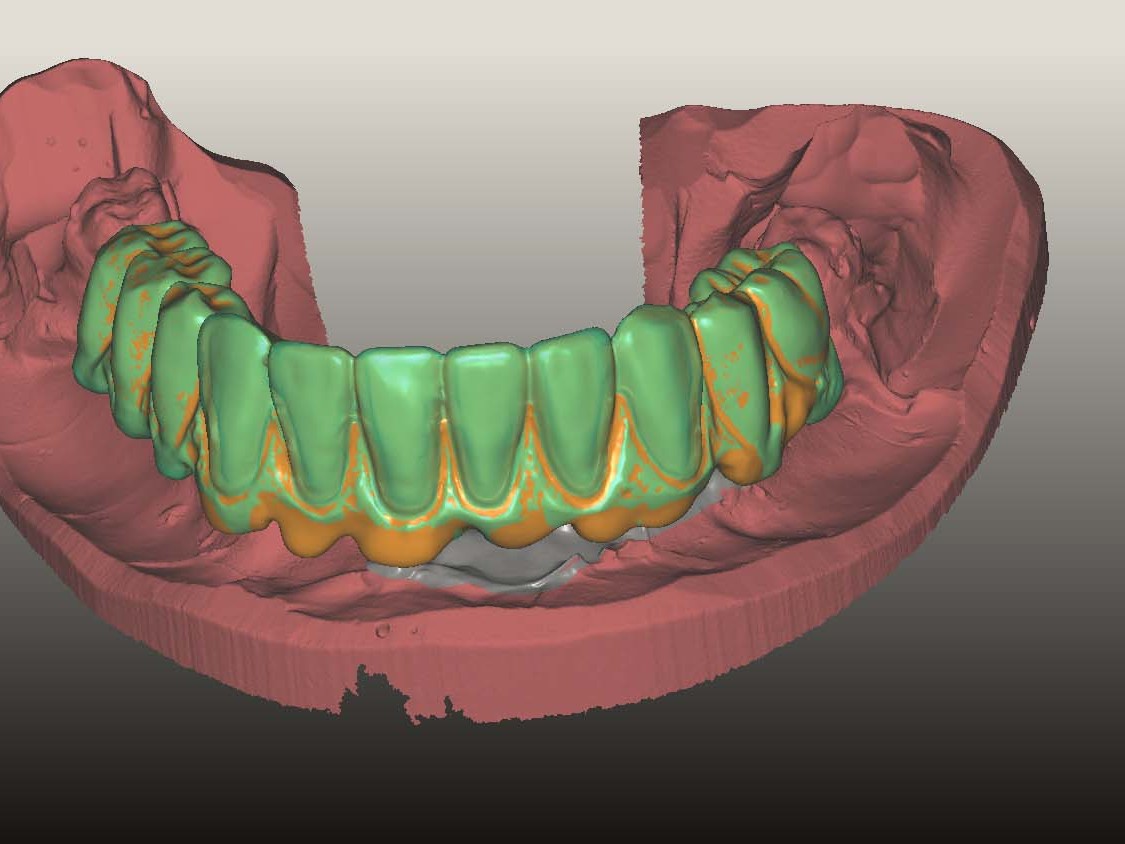

Mit dem Digital Immediate Smile Model von Materialise Dental ist es erstmals möglich, die aus der DVT-Planung stammenden Daten als offenen STL-Export zu erhalten. Neben der Information über die Position der Implantate und den dazugehörigen Abutments enthält der STL-Export auch „gematchte“ Optical Scan Modelle (Situationsmodelle) (Abb. 4), die mit vielen CAD-Programmen weiterverarbeitet werden können. Zudem wird dem zahntechnischen Labor ermöglicht, ohne Zeitdruck präoperativ ein Sofortprovisorium zu erstellen. In diesem Fall wurden die STL Daten in eine CAD Software geladen. Die Modellation des Provisoriums erfolgte anhand des Situationsscans (Abb. 5). Die verwendeten Retentionskappen für das Ankylos® C/X Implantatsystem wurden virtuell in der CAD Software hinterlegt und mit einem zusätzlichen Platzhalter versehen. Nach Fertigstellung des Designprozesses wurde das Sofortprovisorium auf einer fünfachsigen Fräsmaschine gefertigt und anschließend poliert (Abb. 6). Ferner wurden die Retentionskappen mit 120μm Aluminiumdioxid zur Retentionsvergrößerung angestrahlt. Das so gefertigte Sofortprovisorium wird nach dem chirurgischen Eingriff in der „Passive-Fit-Technik“⁷ intraoral verklebt, um etwaige Abweichungen der Implantatachse und –tiefe auszugleichen und eine Spannungsfreiheit zu gewährleisten⁸.